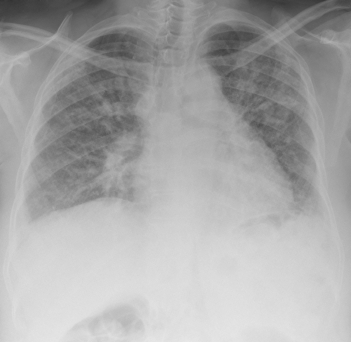

Изучение истории болезни и медицинский осмотр не проводятся. Большинство родов центра экрана для муковисцидоза при рождении. Потом тест может быть сделано для обнаружения повышенной солености кожи часто встречается. Другие тесты, будет сделано в случае необходимости для выявления инфекции и повреждения легких, кишечника и придаточных пазух носа испытали.

Ранняя диагностика и агрессивное лечение может значительно продлить жизнь больного. Лечение включает антибиотики для синуса и легочных инфекций, а некоторые пациенты принимают эти препараты все время, чтобы помочь предотвратить рецидивирующие инфекции. Другие препараты включают бронходилататоры, и слизи истончение наркотики. Пищевые добавки и ферменты поджелудочной железы может помочь уменьшить некоторые из недостаточного питания испытали. Грудь ударных может помочь разрушить слизи и предотвратить распад легких и повреждения. Иногда пересадку легких и кишечника операции не требуется.